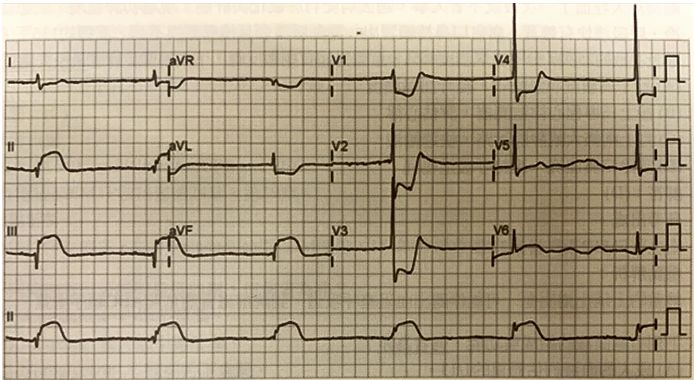

40.下列有關量張十二導程心電圖的描述何者為非? (A)此為Sinus Bradycardia (B)心率約每分鐘30~36次 (C)心臟下壁的急性心肌梗塞 (D)V1~V4的ST段下降是對應變化(reciprocal changes)